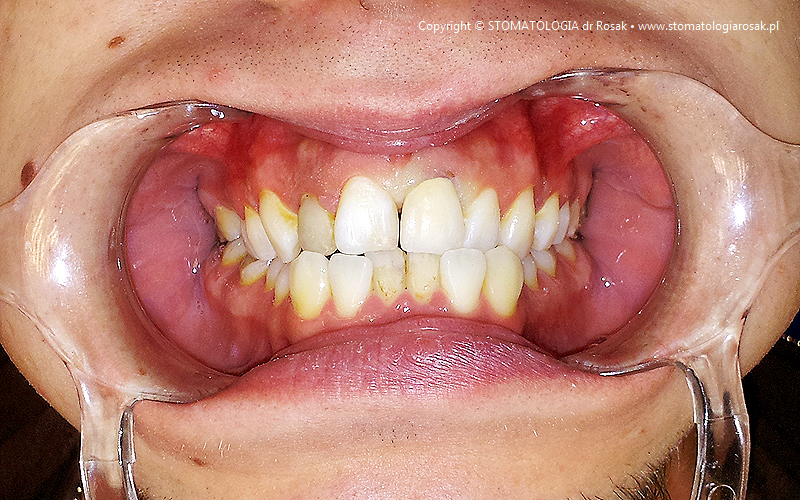

| 9a. Przed leczeniem |

9b. Gotowe korony i mosty porcelanowe na górze

(trójkę górną prawą pacjent zażyczył sobie nie korygować)

oraz w żuchwie tzw. czapeczki pokrywające oraz zatrzaski kulowe dla lepszego utrzymania protezy ruchomej dolnej |